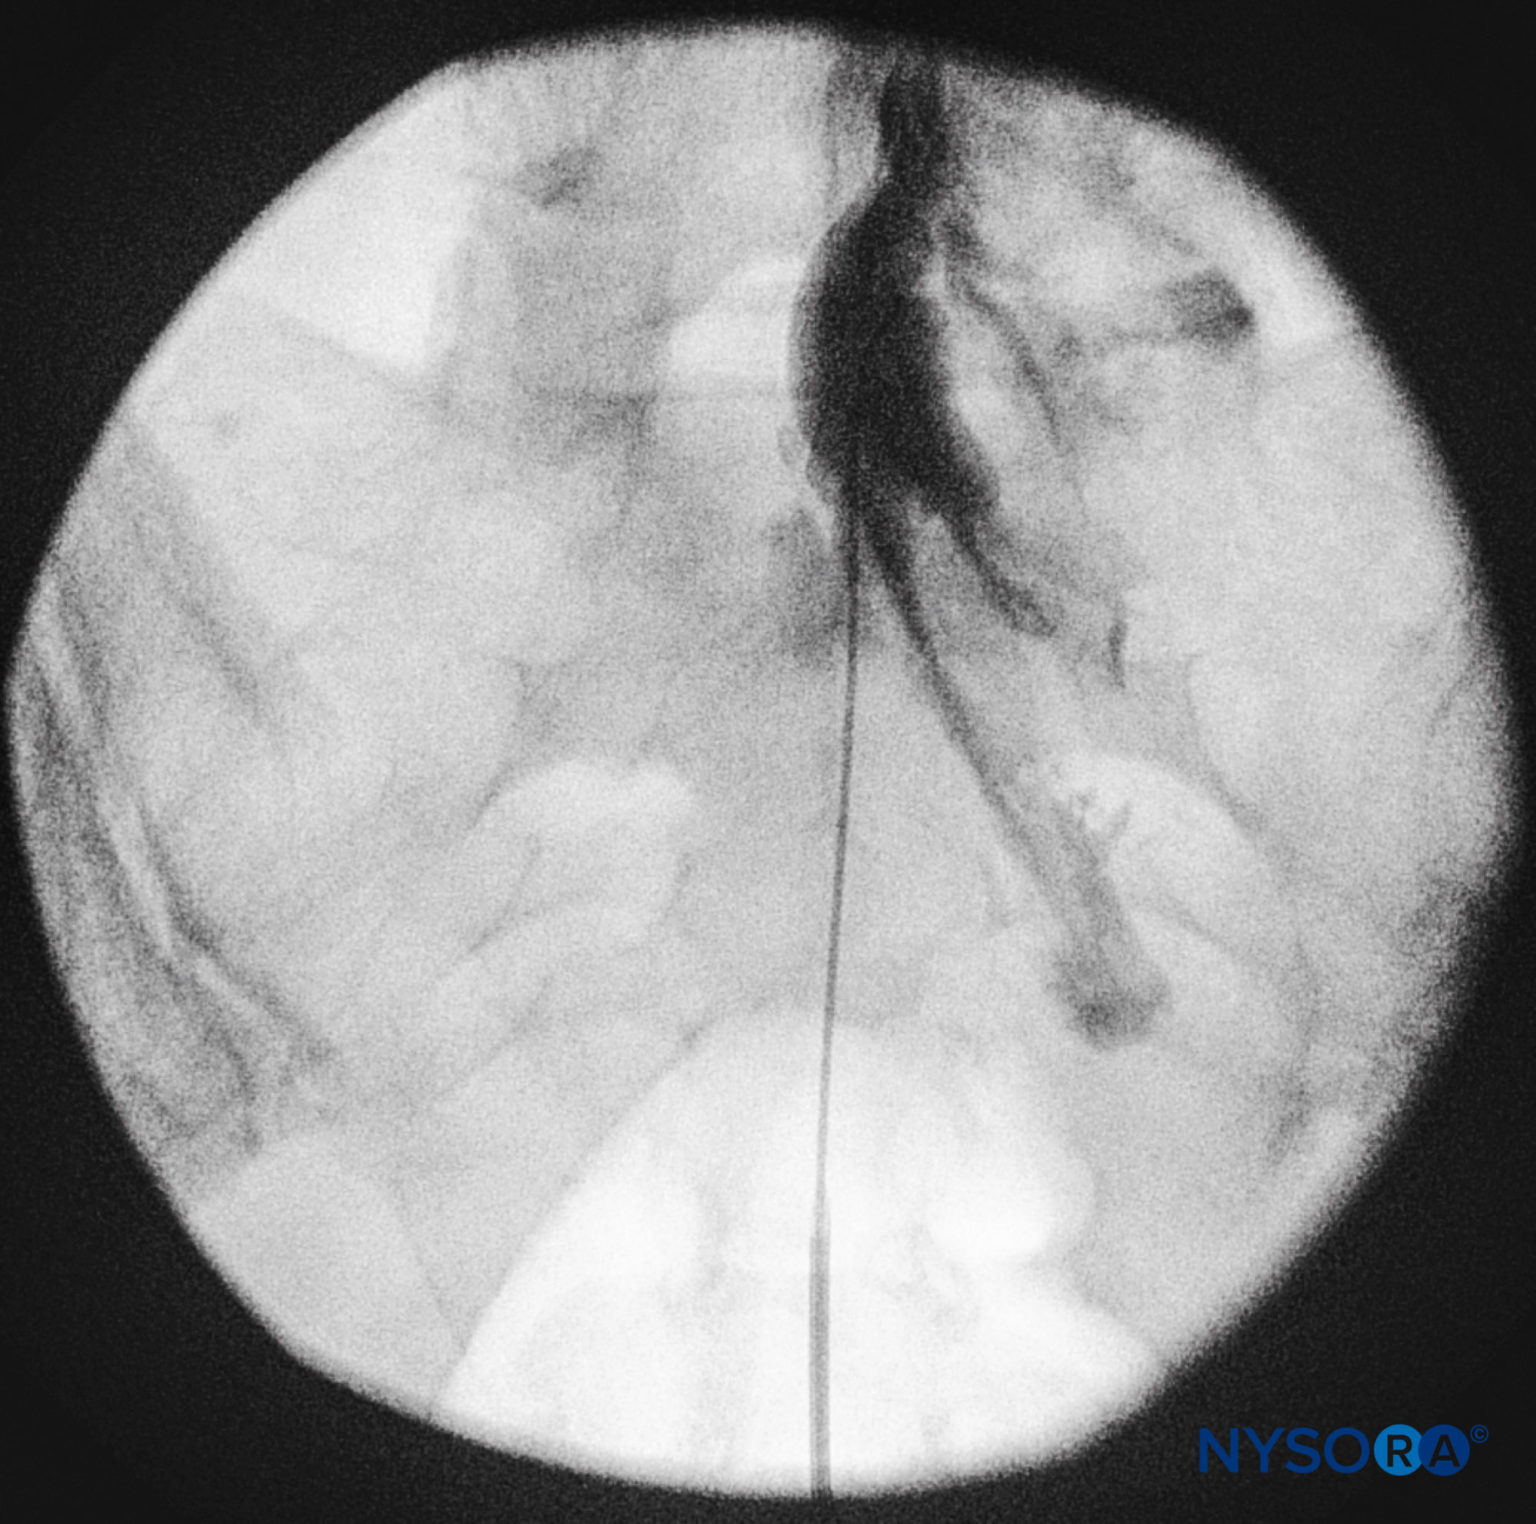

From www.nysora.com

regionalanesthesiaanteroposteriorfluoroscopicimagedepicting Epidural Catheter Radiopaque the portex catheter (group a) or the arrow catheter (group b) was inserted through a single epidural space from th7. transparent polyurethane epidural catheter with radiopaque line. the epidural catheter was not visible with fluoroscopy and it was impossible to inject radiopaque dye into the catheter. this article reviews the history of epidural catheter design, focusing. Epidural Catheter Radiopaque.

regionalanesthesialateralfluoroscopicimagedepictingradiopaque Epidural Catheter Radiopaque the epidural catheter was not visible with fluoroscopy and it was impossible to inject radiopaque dye into the catheter. the portex catheter (group a) or the arrow catheter (group b) was inserted through a single epidural space from th7. Lumbar epidural catheters were placed in 20 female patients by a midline technique. transparent polyurethane epidural catheter with. Epidural Catheter Radiopaque.